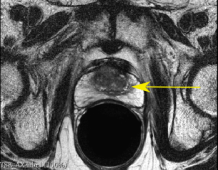

Fig. 4: SR result for anisotropic SRGAN using real data, yellow arrow indicates suspicious cancer region

Figure 4 is an example of axial and coronal views. The HR views portray the difference in resolution between the in-plane axial slice and the coronal and sagittal through-plane slices. The SR views show the anisotropic SRGAN outputs on the real HR data. The arrows in the top row of Figure 4 point to a suspicious region within the axial prostate. The LR axial image obtained by taking a through-plane slice from a coronal volume has lost all information about this region. The SR image is able to reconstruct the high frequency content and provides valuable edge and texture information. The anisotropic SRGAN method is able to improve the through-plane resolution by 8x while incurring only a slight resolution loss in the in-plane slice.